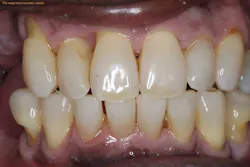

Periodontal desiccation offers many benefits to the patient and clinician. The process of periodontal desiccation works by drying out the plaque biofilm and the necrotic tissue that could remain after periodontal scaling and root planing.2 Once the biofilm matrix is dry, it can no longer remain attached to the tooth’s surface, so it is flushed out of the periodontal pocket. This benefits the patient by reducing the high counts of microorganisms in this localized area.2

Another benefit of periodontal desiccation is that the biofilm cannot grow and divide when desiccated, thus there is a high likelihood that the periodontal bacteria are completely erased in the pocket.2,3